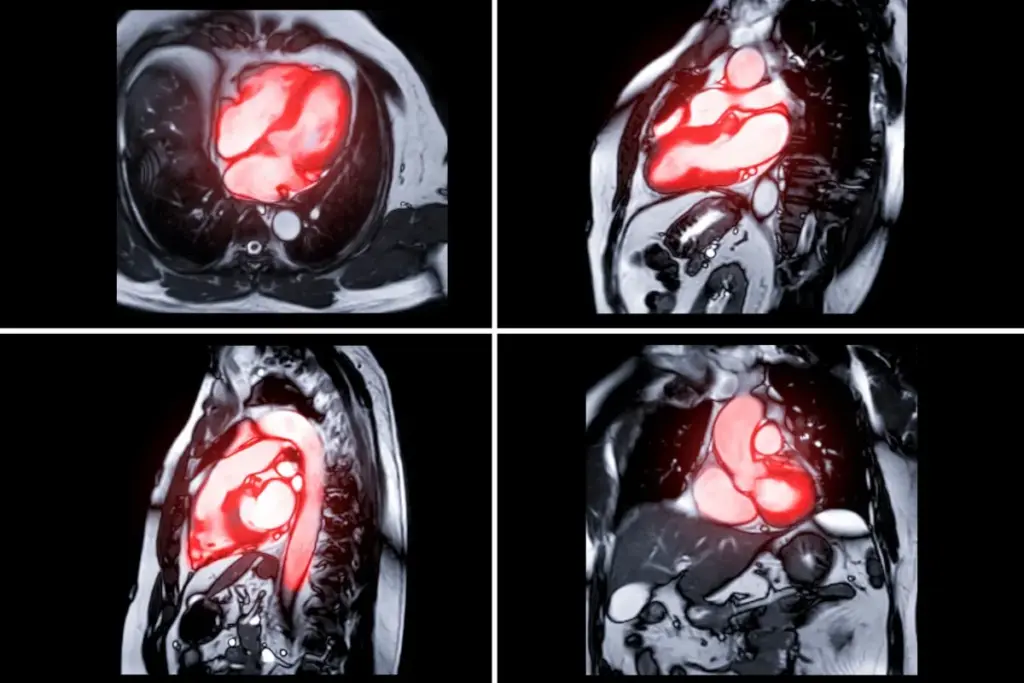

The Role of Imaging in Diagnosing Cardiac Failure

Imaging techniques like X-ray are key in diagnosing cardiac failure. They help doctors understand heart health. This information is vital for making the right decisions for patient care.

Overview of Imaging Techniques

Many imaging methods are used to spot cardiac failure. These include X-ray, CT scans, MRI, and echocardiography. Each method has its own benefits and is picked based on the patient’s needs.

- MRI: Shows the heart’s structure and how it works in high detail.

MRI and CT Scans

Magnetic Resonance Imaging (MRI) and Computed Tomography (CT) scans give detailed heart images. MRI is great for seeing the heart’s structure and function without radiation. It can spot issues like scar tissue and cardiomyopathy.